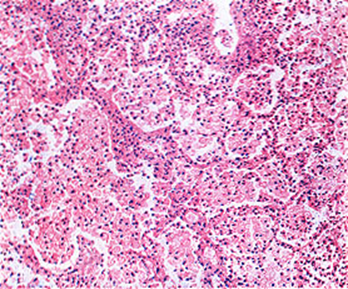

1.以渗出为主的病变

①出现于疾病的早期或机体抵抗力低下,菌量多,毒力强或变态反应较强时。

②主要表现为浆液性或浆液纤维素性炎。

病变早期局部有中性粒细胞浸润,但很快被巨噬细胞所取代。在渗出液和巨噬细胞中可查见结核杆菌。

③好发于肺、浆膜、滑膜和脑膜等处。

镜下:典型结核结节(tubercle)中央有干酪样坏死,周围由上皮样细胞、朗格汉斯巨细胞加上外周局部集聚的淋巴细胞和少量反应性增生的成纤维细胞构成。